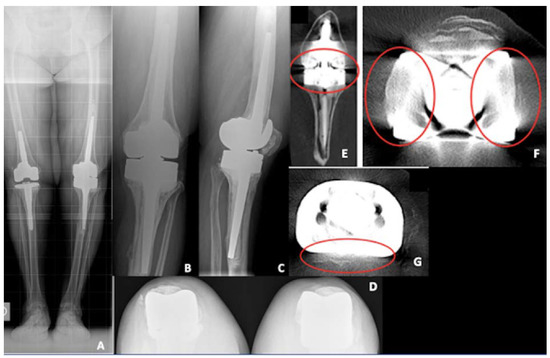

3.5. Clinical Case: Complex Revision TKA

A female patient, 66 years-old, slightly overweight (BMI 27 kg/m2) and without significant comorbidities, underwent right and left revision TKA for aseptic loosening with a rotating hinge implant. A couple of years later, she developed progressive left knee pain, in which an Endomodell® (Waldemar Link GmbH, Hamburg, Germany) rotating hinge was implanted. The pain was mainly located at the tibial side. At the clinical evaluation, there was one single anterior scar, no signs of infection, ROM was 0–100°, tibial pain was evocated during palpation and the knee was stable. PJI was firstly ruled out with negative lab test and negative white blood cells (WBC) and polymorphonucleate (PMN%) count in the synovial liquid.

Standard X-rays demonstrated a varus lower limb alignment, tibial aseptic loosening, previous augments on the tibial side, full stem cementation, acceptable patellar height and a huge bone loss was expected, especially on the tibial side. A CT scan was also performed, and bone loss was confirmed on the tibial side, even if it was difficult to evaluate due to the presence of multiple artifacts. Figure 6 shows pre-operative X-rays and CT scan.

Figure 6. Pre-operative X-rays of the re-revision TKA case. (A) Long-leg weight bearing view; (B) antero-posterior view; (C) lateral view; (D) patellar view; (E) coronal view of a computer tomography (CT) scan demonstrating tibial bone loss (red circle); (F) coronal view of a CT scan demonstrating femoral artifacts (red circle); (G) axial view of a CT scan demonstrating tibial artifacts (red circle).